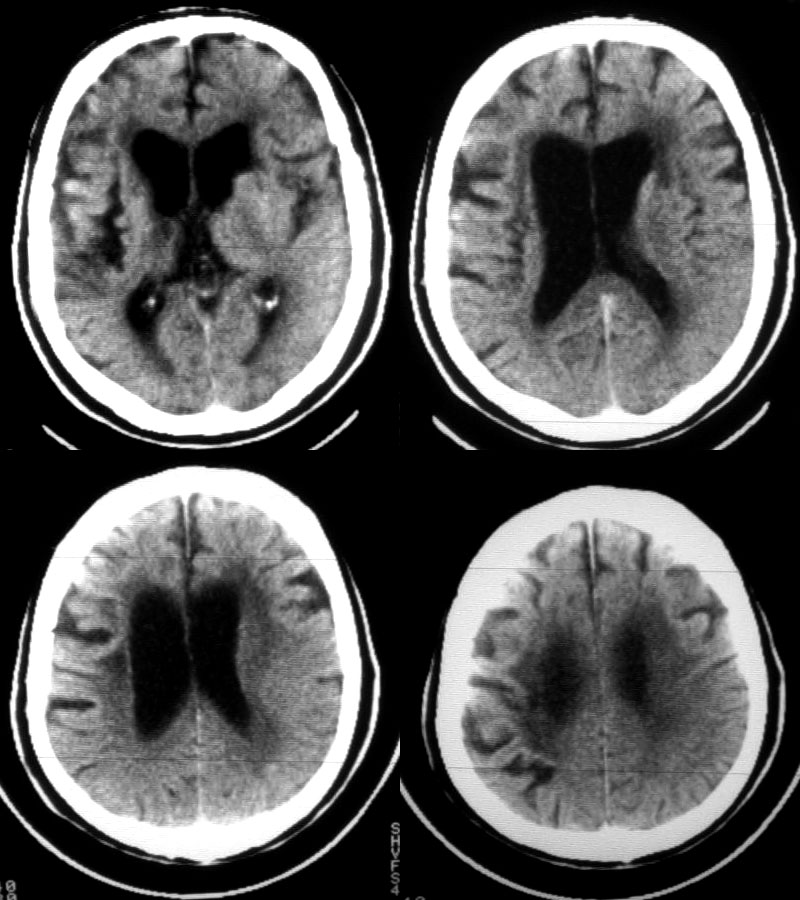

男72岁突然昏迷10小时,既往有脑梗塞病史10余年。左侧大脑梗塞?

1:右基底节区腔隙性脑梗塞

2:皮层下动脉硬化性脑病、脑萎缩(髓质型)。

老年性三联症(多发腔隙性脑梗塞 脱髓鞘变性 脑萎缩)。

1)老年性三联症(多发腔隙性脑梗塞 脱髓鞘变性 脑萎缩)。

2)除此之外,发现左侧大脑半球密度略低于右侧,脑回脑沟略变细变浅,轻度占位性改变,同侧侧脑室较对侧略窄,再者结合病人病逝,昏迷10小,我觉得24小时后复查ct以出外左侧大脑中动脉脑梗塞。

老年脑,软化灶,左侧 新鲜梗塞。(密度低,周边模糊)